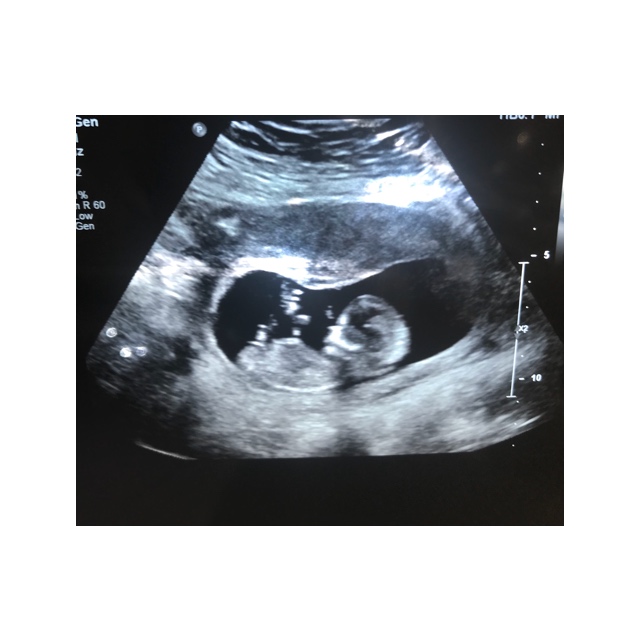

I just had my 12 week scan yesterday. I was 12 weeks 4 days but baby was measuring 13 weeks 1 day.

I didn’t get many good photos & I’m not even sure if the nub is pictured. I’d love any guesses that you might have :)

Attachment 42166Attachment 42167Attachment 42168